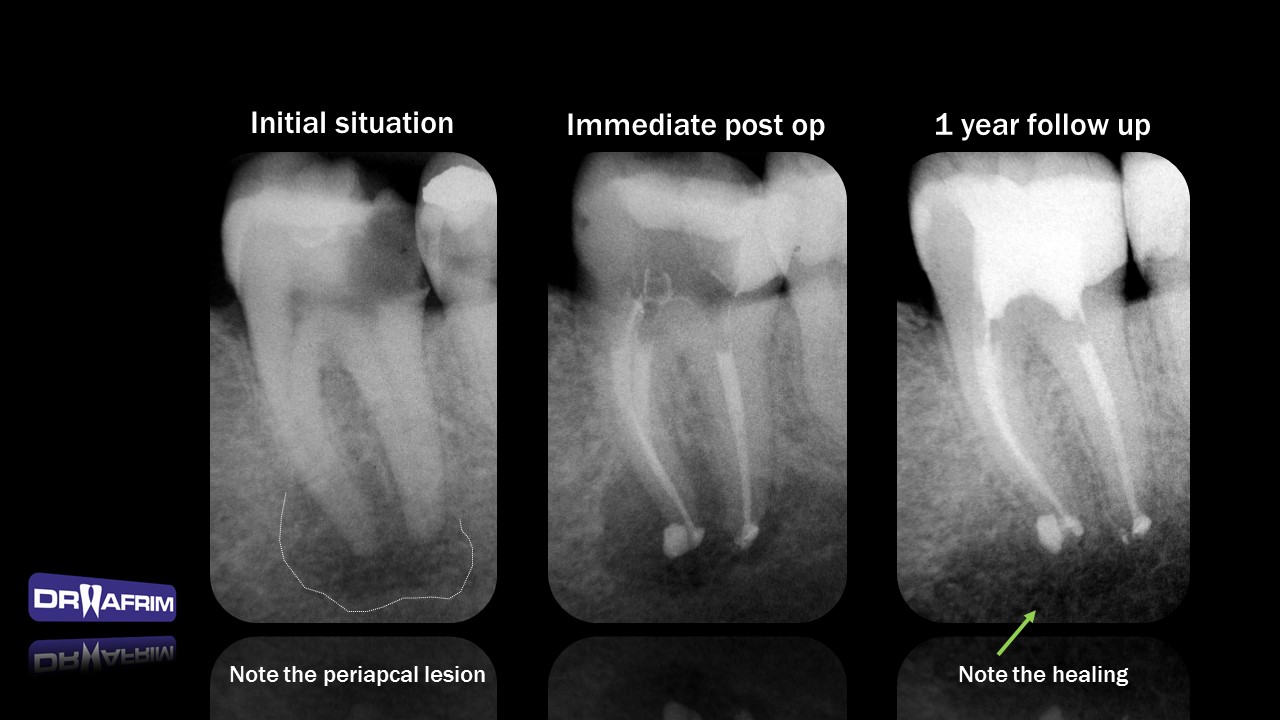

Teeth with large periapical lesions does not necessary need to be submit to surgery or extraction. Endodontic treatment is conservative approach which can lead to successful healing, without surgical trauma or losing the tooth. Regular follow up is necessary.